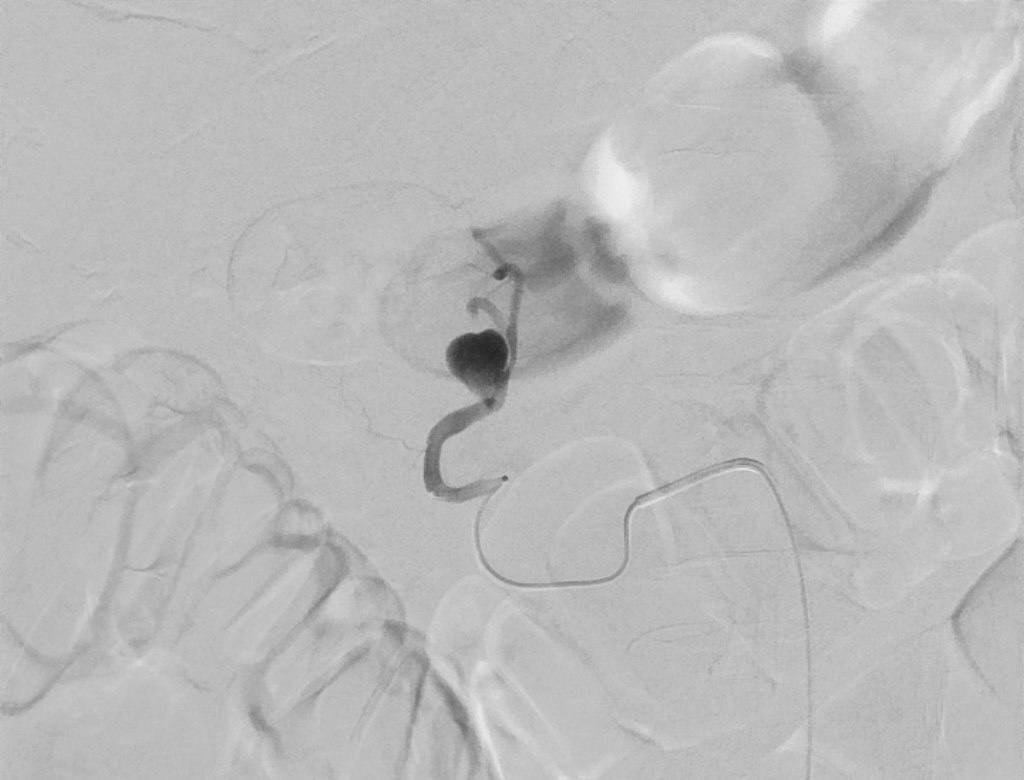

Рентген-хирурги провели внутрисосудистую операцию с применением специального состава, обычно используемого в нейрохирургии. Уникальность метода заключается в том, что клей позволяет точечно воздействовать на мелкий сосуд. Соприкасаясь с тканями и кровью, состав в тот же миг кристаллизуется и крепко запечатывает стенку сосуда. К тому же состав имеет цвет, что позволяет хирургам видеть четкую картину происходящего на рентген-аппарате.

Неотложная помощь потребовалась 74-летнему пациенту с тяжелой патологией. В анамнезе у мужчины имелся панкреонекроз, воспаление в брюшной полости и выраженный болевой синдром. Медики провели компьютерную томографию, грамотно поставили диагноз и выполнили сложную операцию. Однако в ходе лечения была обнаружена аневризма верхней брыжеечной артерии, из-за которой появилось массивное кровотечение.

Пациента срочно перевели в отделение рентгенохирургических методов диагностики и лечения. Через прокол в бедренной артерии врачи добрались до опасного участка и ввели адгезивное средство, моментально «заклеившее» поврежденную стенку сосуда изнутри. Вся операция заняла не более 40 минут. Сейчас пациент восстанавливается и готовится к дальнейшему лечению.